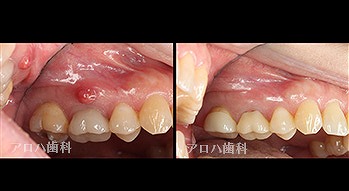

case3

再根管治療

瘻孔の消失

1年予後

外科的歯内療法

case8

自費の補綴

頬側に瘻孔